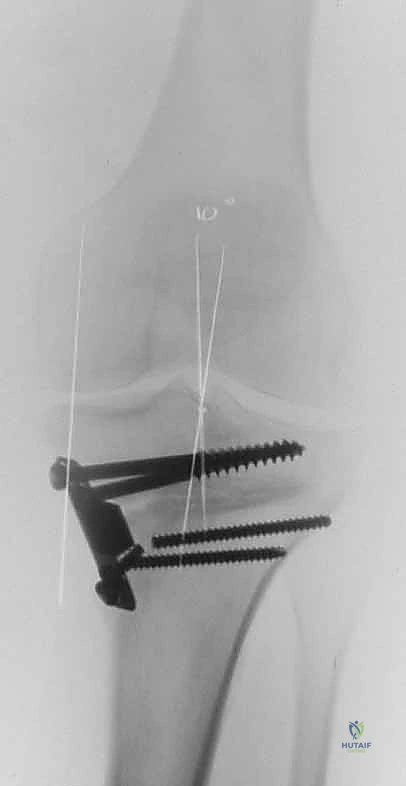

B.

Intraoperative final AP radiograph.

C,D.

Postoperative AP and lateral radiographs.